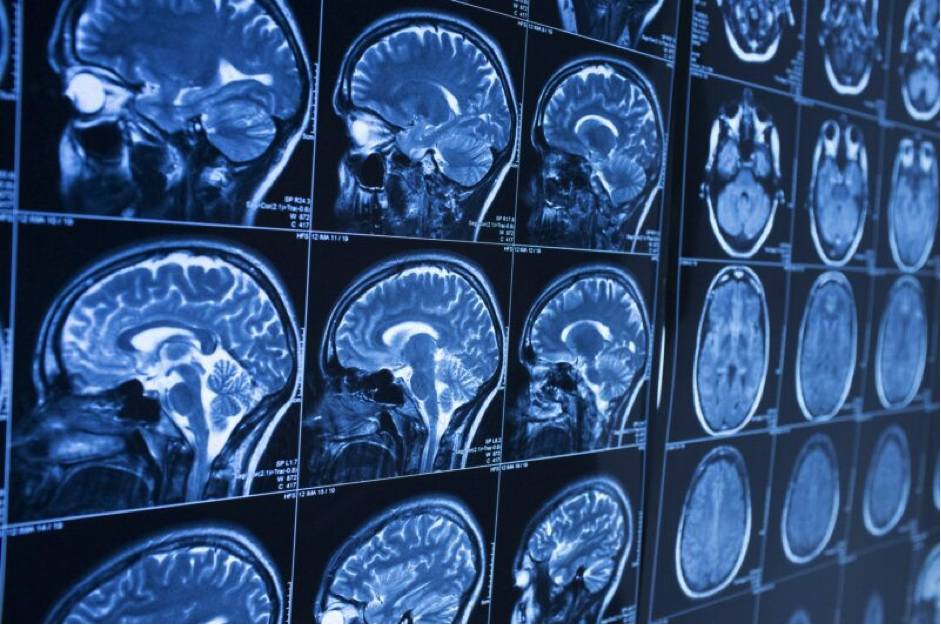

What to Expect Decades After a Traumatic Brain Injury

Recovering from a traumatic brain injury can take months or even years. While many people regain strength and function over time, the effects of the injury often last much longer than expected. Some people begin to notice new or recurring health issues even decades later.

Long after the initial recovery, traumatic brain injury symptoms can still affect memory, mood, coordination, and overall quality of life. These symptoms may change or worsen with age, making long-term care and awareness just as important as early treatment. Understanding what can happen years after the injury helps survivors and families prepare for the future.

A traumatic brain injury, or TBI, happens when the brain is damaged by a sudden force, such as a blow to the head or a violent jolt. Even after visible healing, the brain’s delicate tissue may remain vulnerable.

Research suggests that a history of TBI increases the risk of developing neurodegenerative diseases such as Alzheimer’s or Parkinson’s later in life. This is because brain injuries can cause long-term inflammation or changes in brain structure that develop slowly over time.